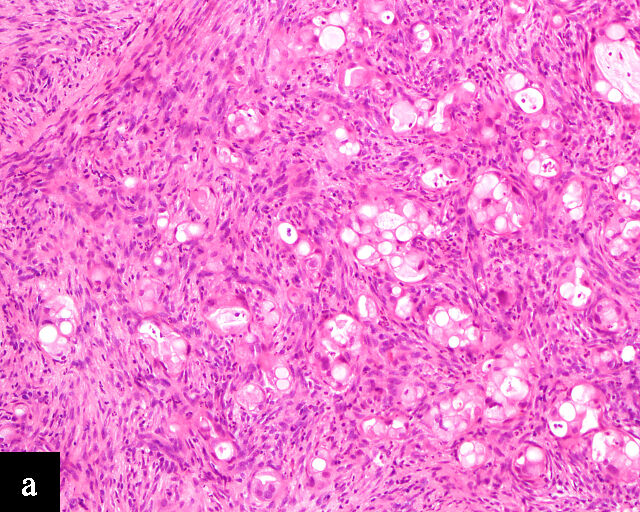

3

Immunohistochemical profile of HPV-independent cervical carcinomas. (a,b) Clear cell adenocarcinoma. (c,d) Gastric-type adenocarcinoma. HPV-independent cervical carcinomas do not show p16 diffuse expression (a,c) and are PAX8 positive (b,d). Magnification ×20.

Clear cell adenocarcinomas of the cervix follow a bimodal age distribution. The first peak is observed at late adolescence/early adulthood13,14 and is associated with in-utero exposure to diethylstilbestrol (DES). The median age at presentation for clear cell adenocarcinoma not related to DES exposure is 48 years15 and constitutes the second peak. Its histological appearance resembles that of clear cell adenocarcinomas from other parts of the female genital tract (uterine corpus and ovaries), in particular tumor cells displaying overt nuclear atypia and a characteristic clear cytoplasm, arranged in variable destructive growth patterns16 (Figure 2a). Clear cell adenocarcinomas of the cervix share common immunophenotypic features with upper female genital tract carcinomas, notably PAX8 positivity and non-diffuse p16 expression17 (Figure 3a,b). Limited data from case series indicate that mutations in CMTM5 and WWTR1 are relatively frequently detected in clear cell adenocarcinomas of the cervix.18,19

Gastric-type adenocarcinoma of the cervix produces neutral mucin and is termed ‘gastric-type’ because neutral mucin is commonly found in gastric adenocarcinomas.27 Its phenotypic resemblance to gastric adenocarcinoma can also be seen in its clear-to-pale eosinophilic, abundant cytoplasm28 and expression of HIK1083 (gastric O-glycan),29 MUC6 (gastric mucin)30 and TFF2 (gastric mucosal peptide).31 As compared to other HPV-independent adenocarcinomas, PAX8 expression is variable in gastric-type adenocarcinomas32 (Figure 3c,d). Mutations in TP53, CDKN2A, KRAS, ERBB2 and ERBB3 (≥10%)33,34 are found in gastric-type adenocarcinomas.